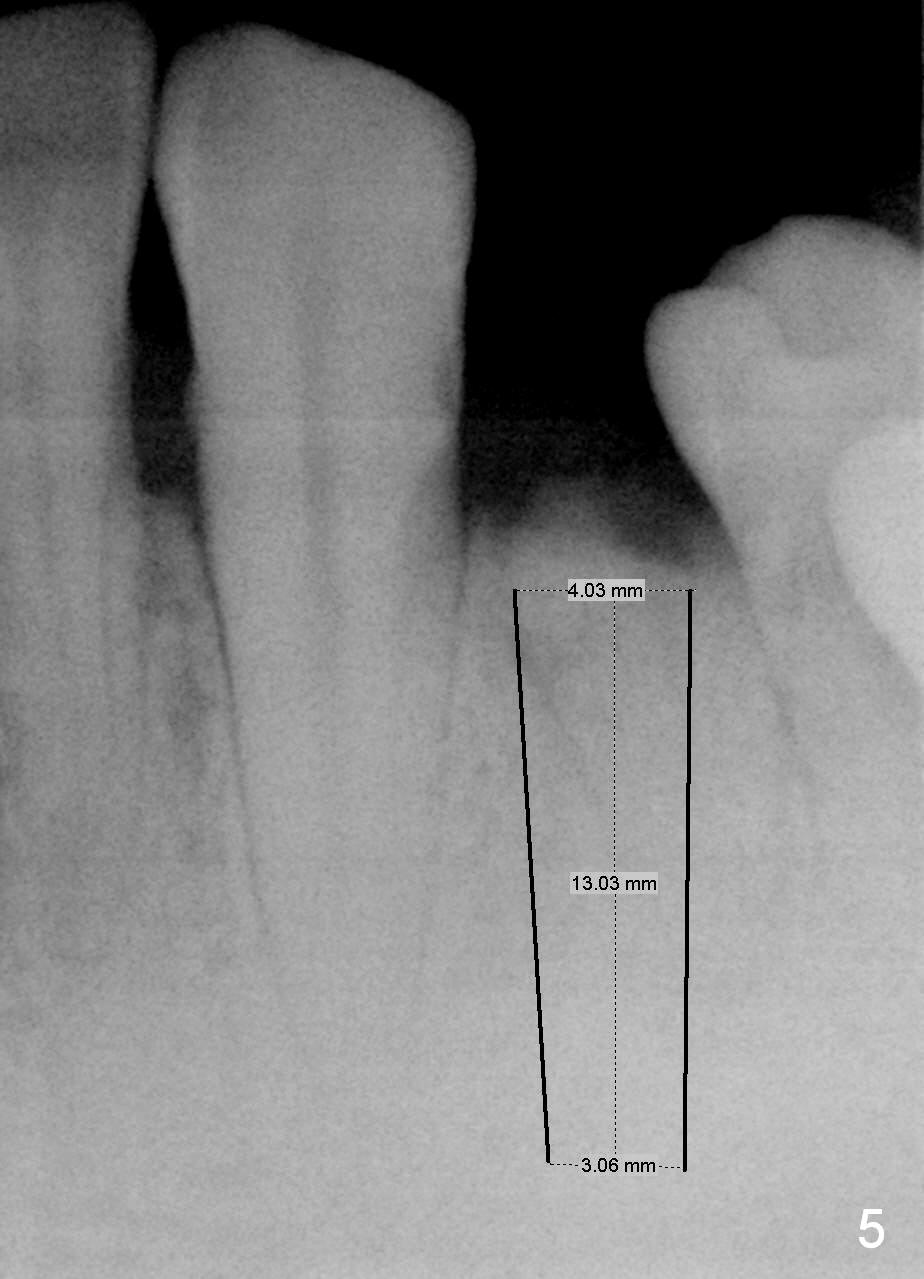

A 48-year-old man requests restoring the fractured tooth #21 (Fig.1). The socket seems to be oblique (Fig.2, no Antibiotic). Also considering the thin buccal plate, the initial osteotomy should be established in the mesiolingual slope (Fig.3). Change the trajectory once the entry is made (Fig.4) and take PA for confirmation. A 4x13 mm implant is to be placed (Fig.5). Why should the implant placed lingually? In fact the implant is placed too lingually. What is the reason?